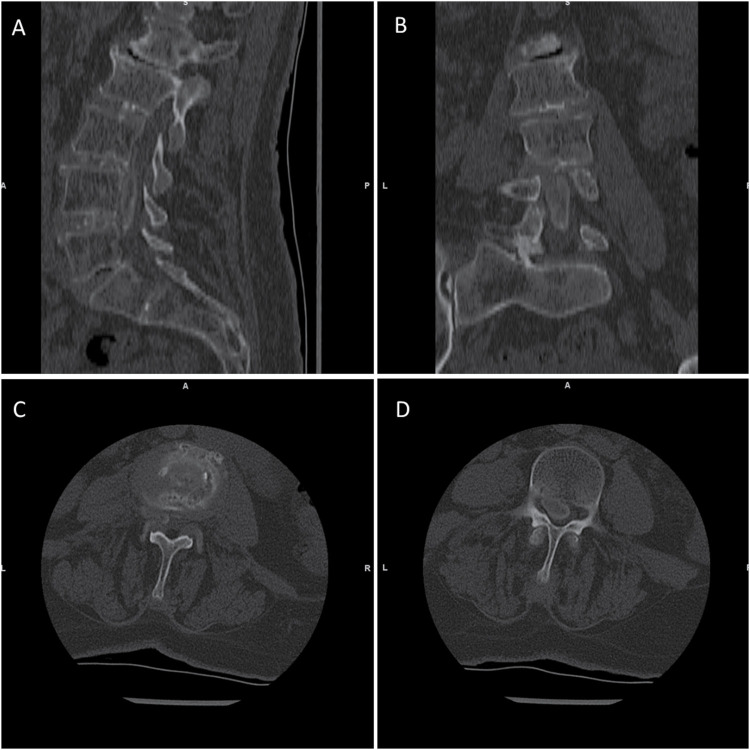

Case description: A 79-year-old woman with a 3-year history of low back pain presented with severe left-sided pain and mobility impairment. Initial examination showed lumbar tenderness and normal muscle strength. Computed tomography (CT) and magnetic resonance imaging scans revealed a calcified extradural mass occupying the anterior portion of the lumbar spinal canal, most likely associated with the posterior longitudinal ligament. The patient underwent L3-L5 hemilaminectomies and dorsal spondylodesis, removing a whitish intraspinal mass. Histopathology confirmed CPPD. Post-surgery, the patient experienced initial pain relief but required emergency surgery due to complications. Over the next year, her mobility and pain improved significantly.

Discussion: Spinal CPPD manifests with varied clinical presentations, complicating diagnosis. Imaging reveals calcifications ranging from deposits to mass-like lesions causing compression. CT provides detailed visualization of characteristic calcifications, aiding in diagnosis, while histopathology remains the gold standard. Multidisciplinary collaboration is vital for accurate diagnosis and optimal management.